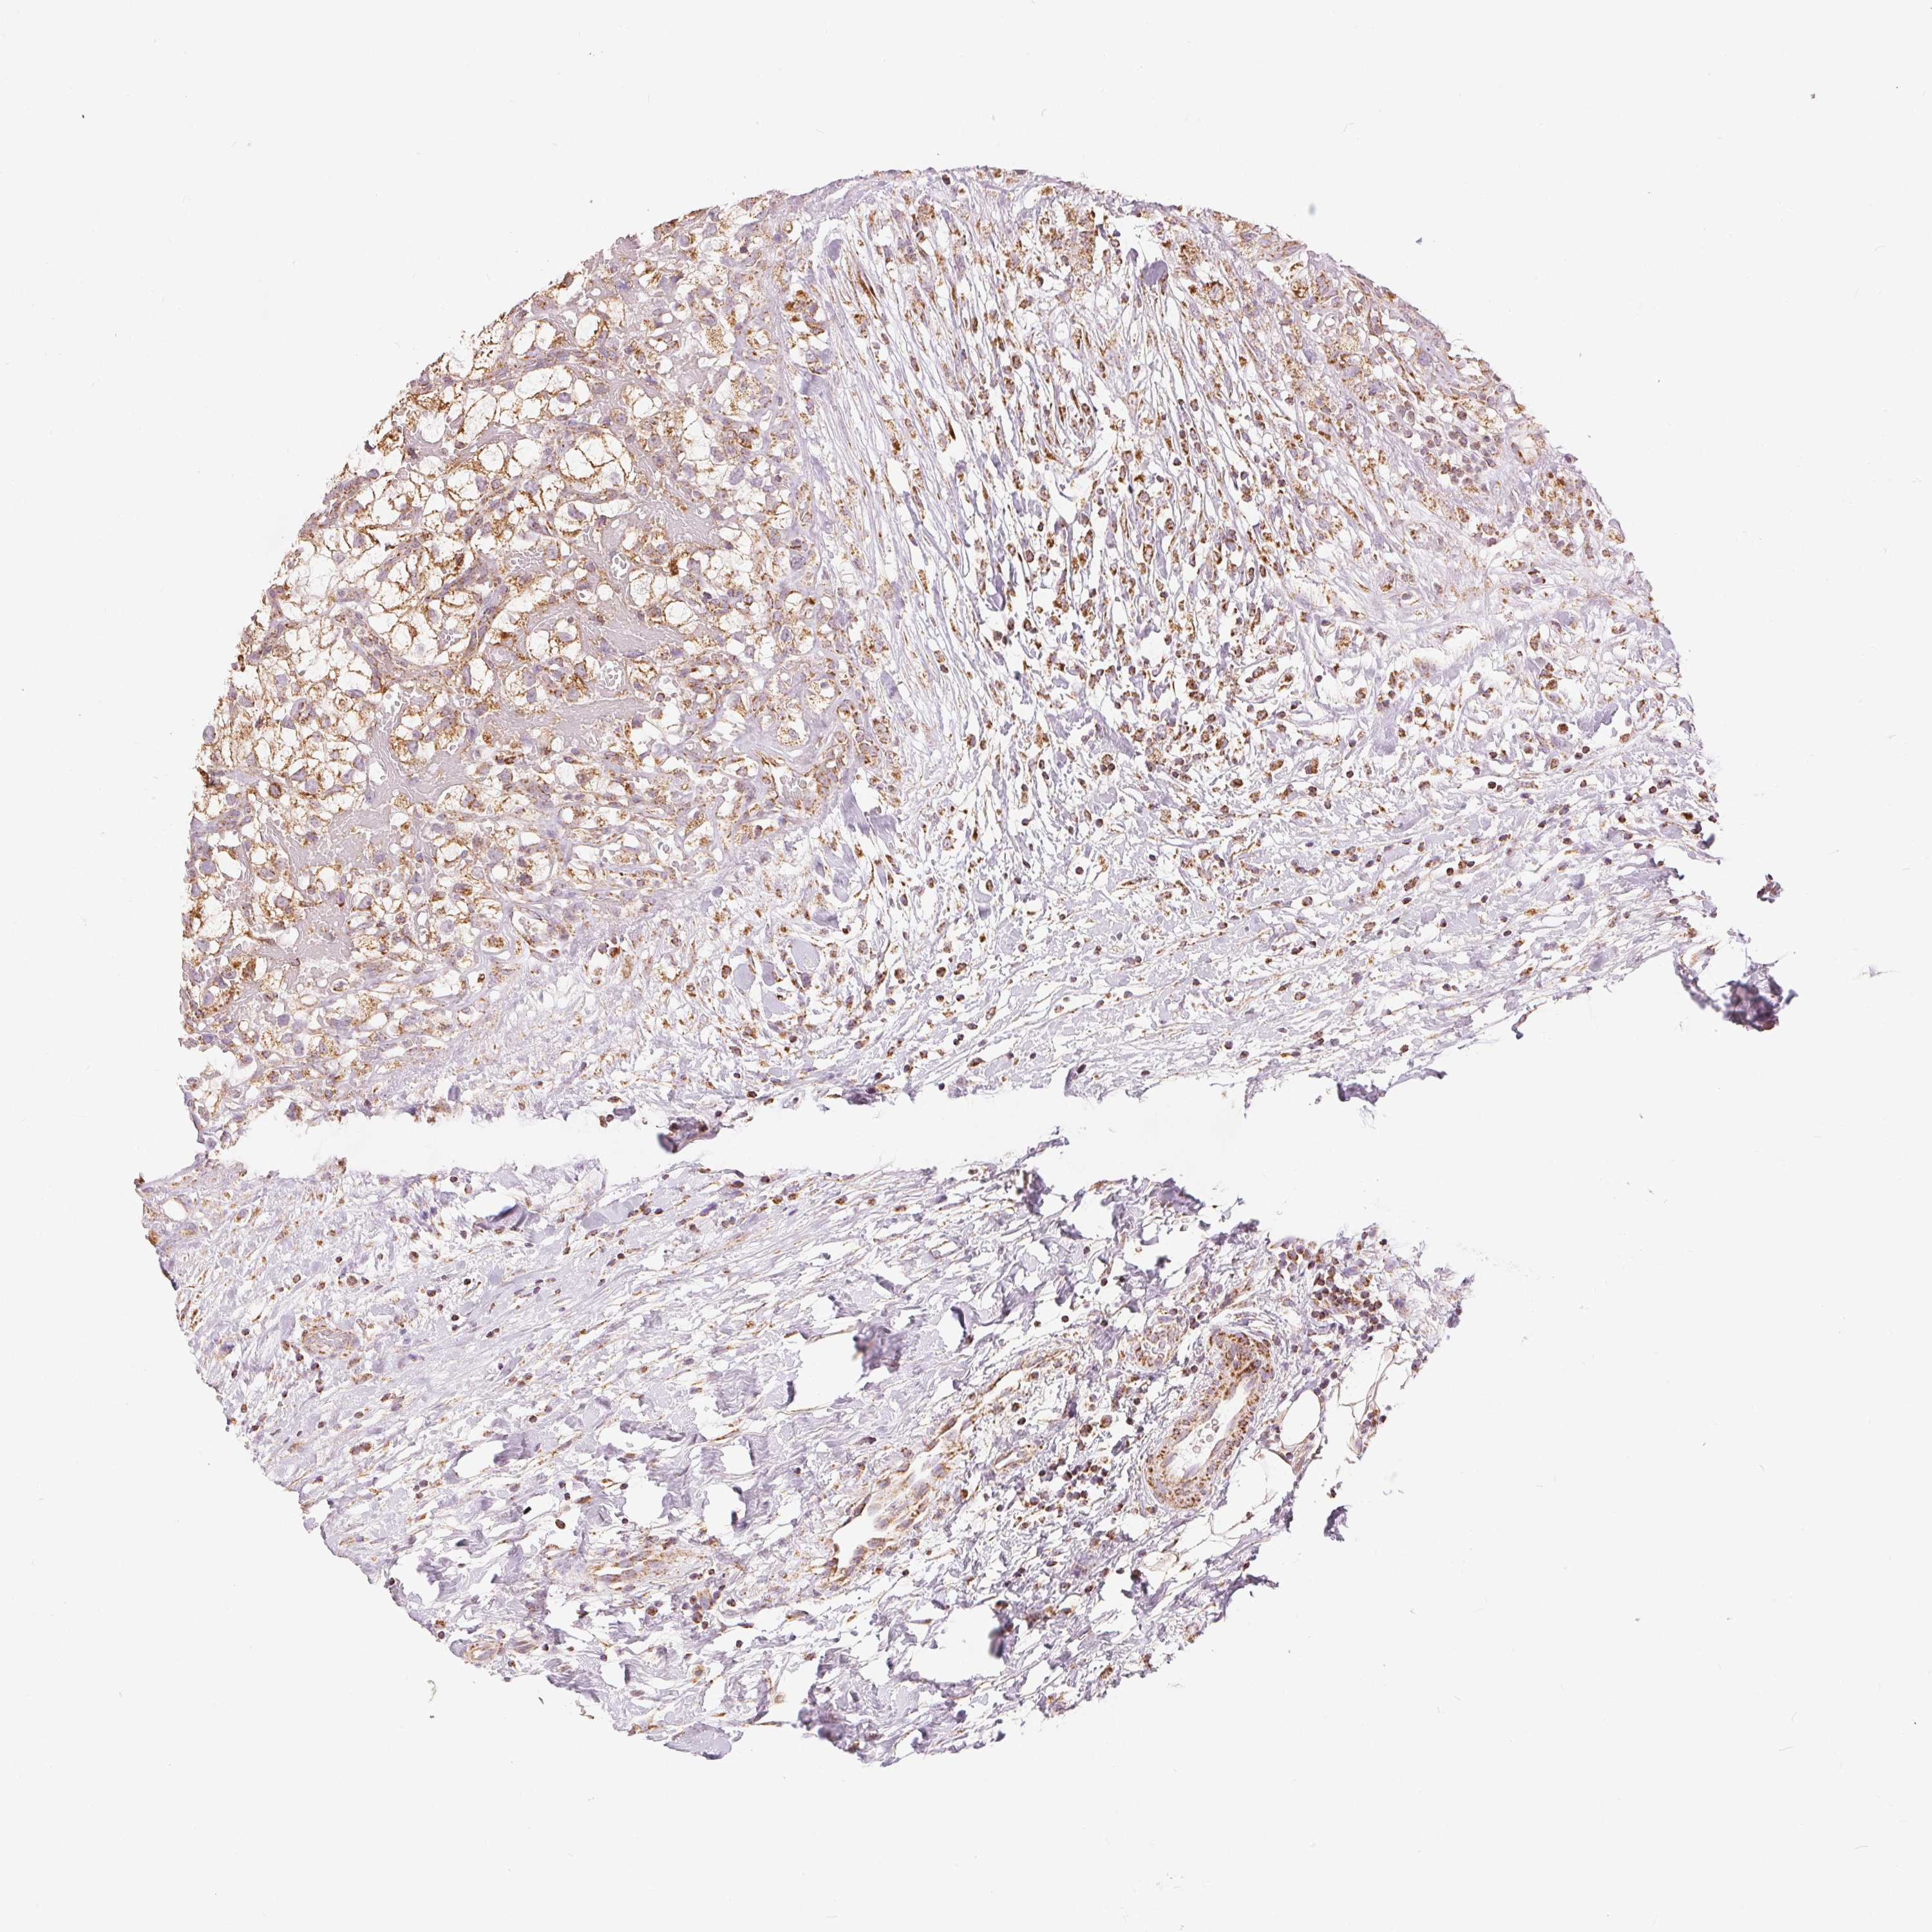

TCGA RNA samplesi

RNA-seq data is reported as average FPKM (number Fragments Per Kilobase of exon per Million reads), generated by the The Cancer Genome Atlas (TCGA) .

Normal distribution across the dataset is visualized with box plots, shown as median and 25th and 75th percentiles. Points are displayed as outliers if they are above or below 1.5 times the interquartile range. FPKM values of the individual samples are presented next to the box plot.

Average pTPM 115.2

Number of samples 100